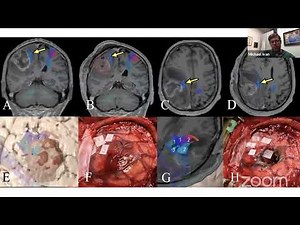

Glioma Surgery - Cerebral

Glioma Surgery - Insular

Surgery - Glioblastoma

MRI - Tumor

Scans - Glioma